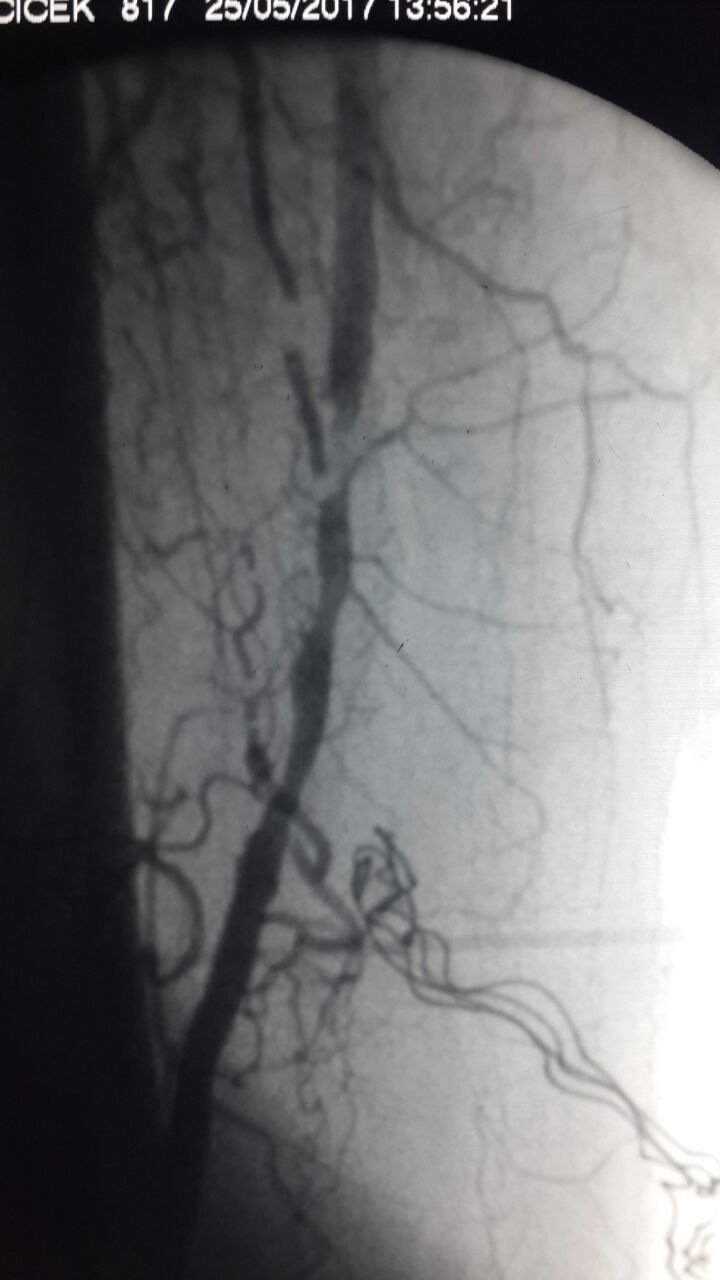

Kardiyoloji Uzmanı Dr. Hakan Göçer, bir hastanın bacak damarının içini tıraşlama (Aterektomi) yöntemi uygulayarak açtı. Uygulama ile bacak damarı tıkalı olan hastanın bacağı kesilmekten kurtarıldı.

Özel Parkhayat Hastanesine başvuran hasta yapılan muayene ve tetkiklerin ardından Dr. Hakan Göçer, yapılan işlemlerle ilgili şu bilgiler verdi: “Aterektomi ya da damar tıraşlama tedavisi atardamar darlık ve tıkanıklıklarını açmak için anjiyo ile yapılan bir yöntemdir. Yöntemin çalışma prensibi, balon ya da stentten farklı olarak damarı genişletmek değil damar duvarında oluşan kireçlenme dediğimiz kısmı tıraşlayarak temizlemektir. Bu nedenle aterektomi yöntemine damar tıkanıklığının tıraşlama tedavisi adı verilir. Aterektomi cihazı son derece incedir ve anjiyoda kullanılan 2-3 mm genişliğindeki kılıf içinden kolaylıkla geçer. İstenen damara yönlendirilir ve burada damarda darlık ya da tıkanıklık oluşturan kısmı tıraşlayarak temizler. Tıraşlanıp alınan doku cihazın haznesinde depolanır ve dışarı çıkarılır. Aterektomi cihazı bir tek kere kullanılmaz. Bir damarı açmak için 7-8 kere yapılır. Her seferinde damarı tıkayan plaklar yavaş yavaş temizlenerek dışarı çıkarılır. Gerek görülürse damar tıraşlama işleminden sonra o damara balon, ilaçlı balon yapılabilir ya da bir stent yerleştirilebilir. Bazen de damar tıraşlama tek başına o damarı açmada yeterlidir.”